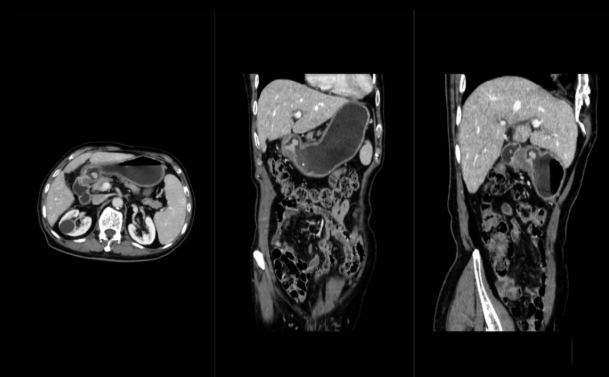

5、腹部高清成像:

了解腹腔脏器有无感染性疾病,如:有无占位,如良、恶性肿瘤,转移性肿瘤等;有无畸形、结石、梗阻、穿孔、积液等;炎症、结核、脓肿等。